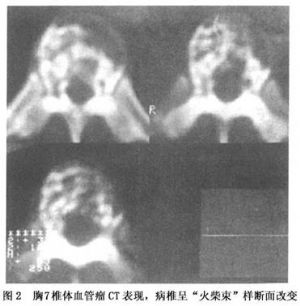

14.4 椎體血管瘤的CT和MRI的表現

CT掃描在診斷椎體血管瘤上具有高度的特異性,病椎呈“火柴束”樣斷面改變(圖2)。與其他骨病變不同的是椎體血管瘤在MRI T1和T2加權像上均呈現信號增強(圖3)。這些斑點的增強的信號與病變的骨的成分相對應,而骨外病竈擴展則在T1加權像不能顯示高強信號。椎體血管瘤運用旋轉回聲技術所進行的MRI檢查,發現病變的不同信號強度很大程度上是由變化的血流速度所決定的,如血管瘤侵入椎管內則CT和MRI均可顯示清楚。